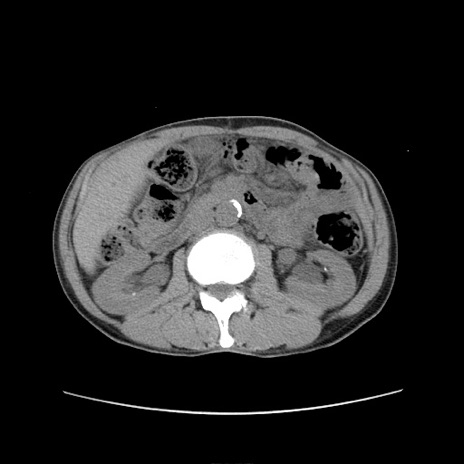

症例11(横断像)

【症例】 60歳代男性

【主訴】 下腹部痛

【現病歴】 本日夜中より下腹部痛の症状認め、受診。

【既往歴】 膀胱癌(膀胱全摘+尿管皮膚瘻術) 、胃癌術後

【身体所見】 BT 35.3℃、PR 58/min、BP 136/98mHg、腹部平坦、軟、腸蠕動音±、ストマ留置あり、左上腹部~正中部に圧痛あり、反跳痛なし。

【データ】WBC 5100、CRP0.01